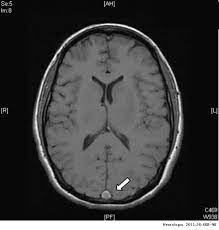

En este estudio de cohorte se encuentra asociación entre la vacuna para el SARS-CoV-2 de Janssen con un aumento de trombosis venosa cerebral. La mayoría de los eventos ocurrieron dentro de los primeros quince días, siendo el riesgo mayor en las mujeres de 30 a 49 años de edad. El riesgo absoluto es bajo y es ampliamente superado por los beneficios estiamdos de la vacuna. JAMA Internal Medicine, 1º de noviembre de 2021.

Este informe sobre los datos de EudraVigilance refuerza los hallazgos anecdóticos sobre la trombosis de la vena cerebral (TVC) después de las vacunas COVID-19. Aunque EMA lanzó alerta solo para  CHADOX1 NCOV-19 (AstraZeneca) y AD26.COV2. S (Janssen) , también Tozinameran (Pfizer-Biontech), CX-024414 (Moderna), tienen complicaciones por TVC, aunque en menor medida.  J Thromb Haemost. 2021

Se presentan los primeros casos en Estados Unidos de esta rara complicación asociada a la vacuna para SARS-CoV-2 de los laboratorios Janssen / Johnson & Johnson.  Tal como ocurrió con los casos europeos atribuidos a la vacuna de Oxford/AstraZeneca, las afectadas son mujeres de 18 a 60 años. JAMA, 30 de abril de 2021.